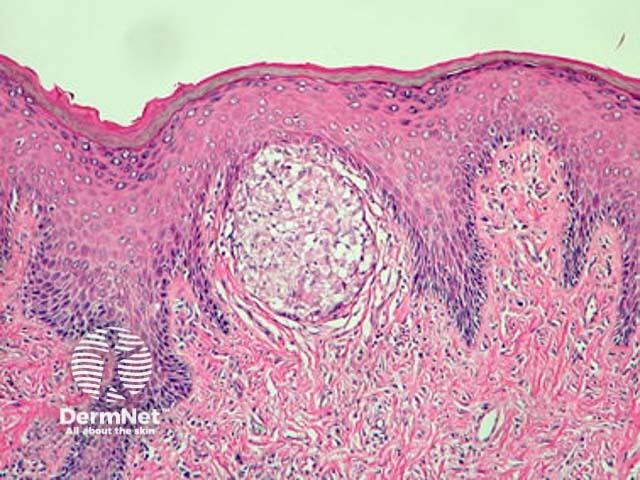

Metastatic Crohn disease is characterised by a dermal granulomatous infiltrate composed of epithelioid histiocytes (figures 1-5). There is an associated infiltrate which is mainly lymphocytic but may be rich in eosinophils. The granulomas may encroach on the epidermis (figure 1). Massive oedema may be seen (figure 2). Ulceration of the overlying epidermis is a common feature (figure 4).

Figure 1